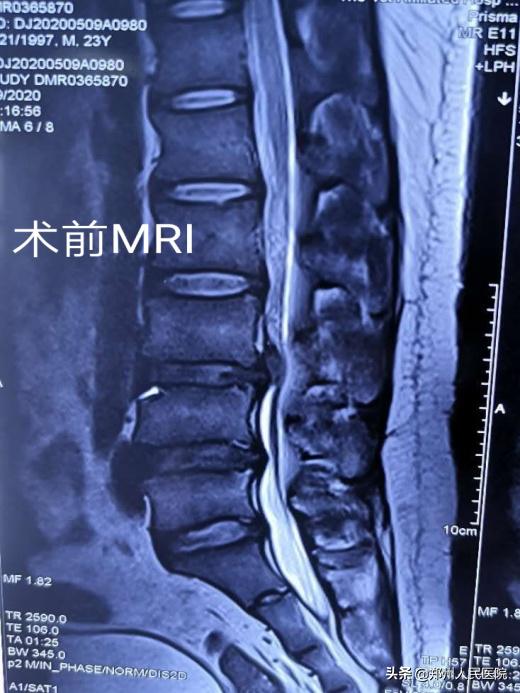

23岁的小葛工作原因需要长期进行弯腰动作,半年前一次劳累的加班过后出现了腰疼的症状,疼痛向双侧臀部及双小腿内侧放射,发作时那种酸困疼痛的感觉,让人难以忍受。

小葛立即去了省内的几家大医院看病,经过各项检查后,他被确诊存在“腰3/4椎间盘突出并髓核脱出,伴有椎管狭窄”。最让小葛纠结的是:每个医院给出的治疗方式不同,各种各样的治疗方式让小葛难以抉择。有的说可以保守治疗,有的说可以做微创手术,有的说必须进行开放手术效果才好。

田明波主任在听到小葛的情况后立即召开了全科室的病例讨论,针对患者的腰椎间盘椎管狭窄病情及患者年龄的特殊性进行反复论证,最终选择使用国内前沿的“单侧双通道UBE脊柱内镜技术”为小葛行手术治疗。

经过充分准备,对小葛实施的“单侧双通道UBE脊柱内镜术”如期举行。手术进行的十分顺利,经过一个半小时,手术成功。